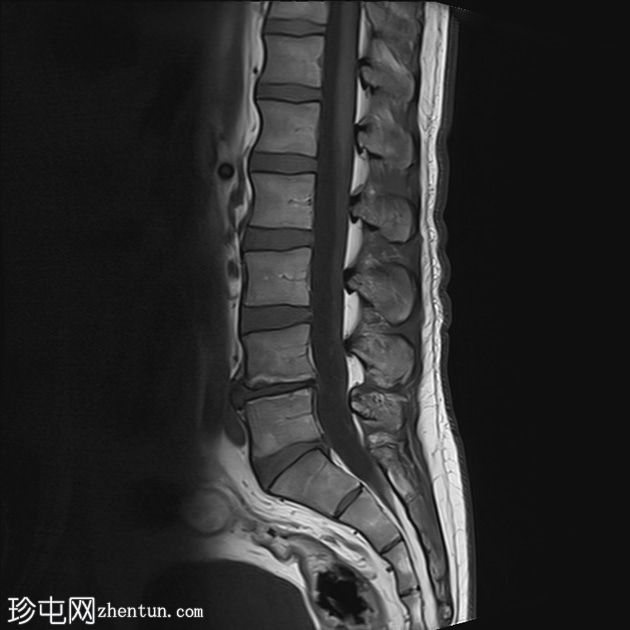

矢状面

T2

T1加权和T2加权序列中L4和L5椎体终板信号强度增加,STIR图像中信号丢失,符合Modic 2型退行

性病

变。L4-5椎间盘退行性病变。

这些发现符合Modic 2型病变,反映了慢性退行性疾病继发的骨髓脂肪替代。此类病变通常与长期机械应力有关。